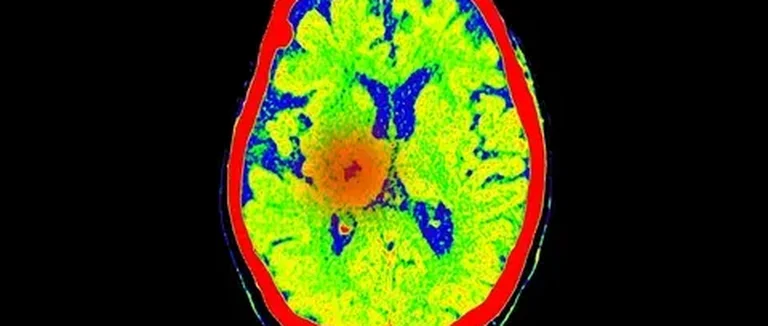

Méthodes Diagnostiques pour les Néoplasmes Kystiques du Cerveau

Imagerie par Résonance Magnétique (IRM)

L'IRM est la meilleure façon d'imagerie pour les lésions kystiques cérébrales. Elle montre en détail les structures du cerveau. Cela aide à déterminer les caractéristiques des kystes.

Avec l'IRM, on peut mesurer la taille et la localisation des néoplasmes kystiques. C'est crucial pour choisir le bon traitement.

Tomodensitométrie (TDM)

La TDM est une technique d'imagerie utilisée en urgence ou quand l'IRM n'est pas disponible. Elle aide à voir les calcifications et les hémorragies liées aux néoplasmes kystiques.

Même si la TDM est moins précise que l'IRM pour les tissus mous, elle est toujours utile pour le diagnostic initial.

Techniques d'Imagerie Avancées

Les techniques d'imagerie avancées, comme la spectroscopie par résonance magnétique et l'imagerie de diffusion, donnent plus d'informations. Elles aident à savoir si une lésion est bénigne ou maligne. Elles évaluent aussi l'agressivité du tumor.

L'utilisation de ces méthodes avancées améliore notre capacité à diagnostiquer et traiter les néoplasmes kystiques du cerveau.